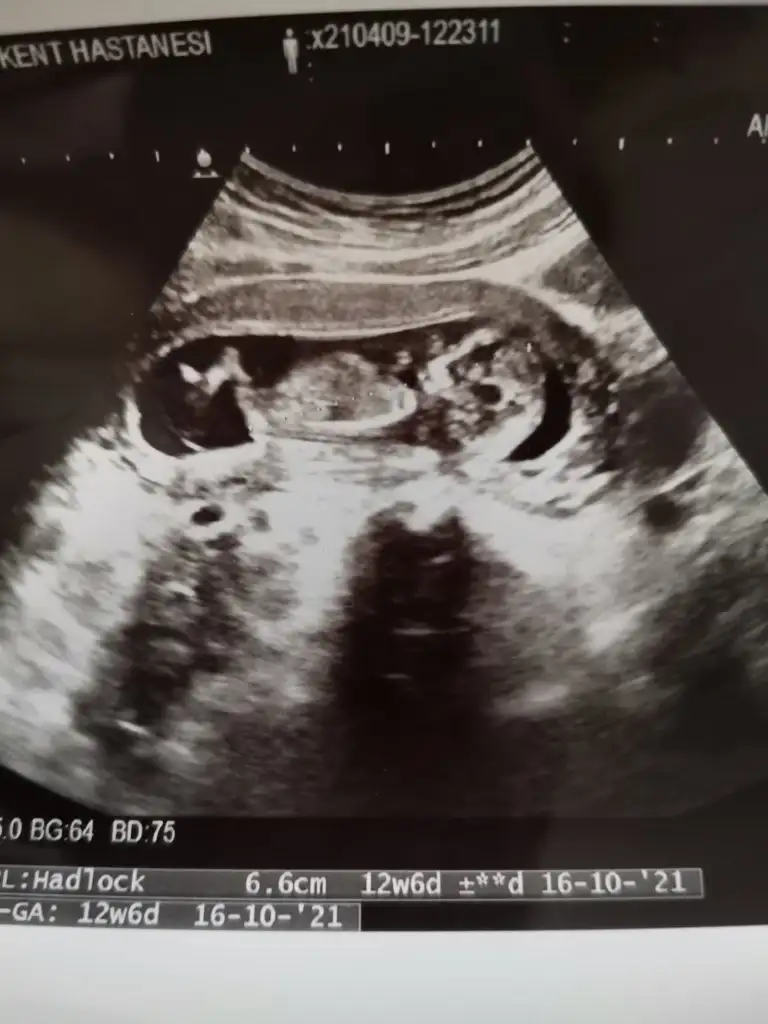

Bizede bakarmısın 12 haftalık bebeğimKız görünüyor

Nubu göremedim varsa USG paylaşın sanki kız tipi varBizede bakarmısın 12 haftalık bebeğim

Kız görünüyorBizede bakabilir misin rica etsem ilk bebeğimizEki Görüntüle 2825129

USG uygun değil olursa paylaşınIkra meyra tahmin cinsiyetine bakabilir misin